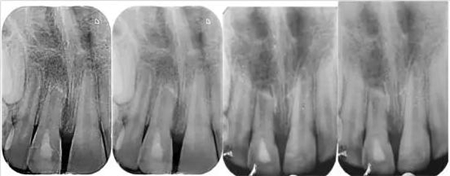

影像學檢查:根尖片以及全景片(圖2)提示牙槽骨骨折,根尖挫入至唇側骨板或鼻底。根尖片提示牙11,12 和21根尖發育不完全,呈喇叭口狀。受累牙的根管壁薄且不完全成形(圖2)。牙片顯示沒有冠折和根折。

( 圖2)

隨訪12個月的X線記錄顯示:在年輕恒切牙的根管壁上有硬組織沉積。從長度上看,牙根并沒有繼續發育,但根尖處硬組織沉積,而且幾乎閉合了(圖 8)。

(圖 8)